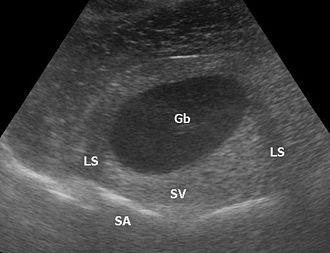

Eine distale Schallverstärkung ist ein übermäßig hell dargestelltes Gewebe hinter (distal) einer Struktur, die wenig dämpft. Allgemein wird, um die Dämpfung des Gewebes auszugleichen und zum Beispiel Lebergewebe über die gesamte Tiefe homogen darzustellen, mit Hilfe der time gain compensation oder auch depth gain compensation, tiefer liegende Signale zunehmend verstärkt. Zum Beispiel bei einer Gallenblase in der Leber ist das Lebergewebe deutlich heller als das restliche Lebergewebe, weil Galle weniger dämpft als Lebergewebe, aber das Gewebe hinter der Gallenblase mit dem gleichen Verstärkungsfaktor aufgehellt wird wie das umliegende Gewebe.

Bei kreisförmig geschnittenen Objekten können die Randstrahlen weggespiegelt werden; dem Bild fehlen dann die Randstrukturen und es kommt zu Abschattungen (engl.: lateral shadowing).